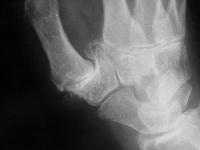

Another thumb, similar changes.